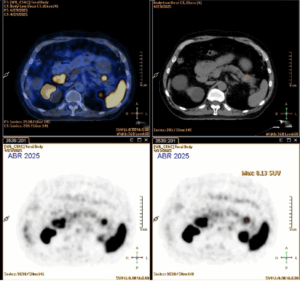

We present the case of a 71-year-old male patient with past medical history significant for radically resected prostate adenocarcinoma in 2019. In 2023, several bone and lung metastasis developed, for which the patient started hormonotherapy (Darolutamide and Leuprorelin), achieving complete response 8 months later.  In 2025, despite PSA blood levels were negative (<0,01ng/dL), a follow-up 68Ga-Prostate-specific membrane antigen (PSMA) PET/TC revealed a de novo nodular uptake in the pancreatic tail (SUV 8,1) (Fig 1.).

Figure 1. 68Ga-PSMA PET/TC: Nodular uptake in the pancreatic tail.